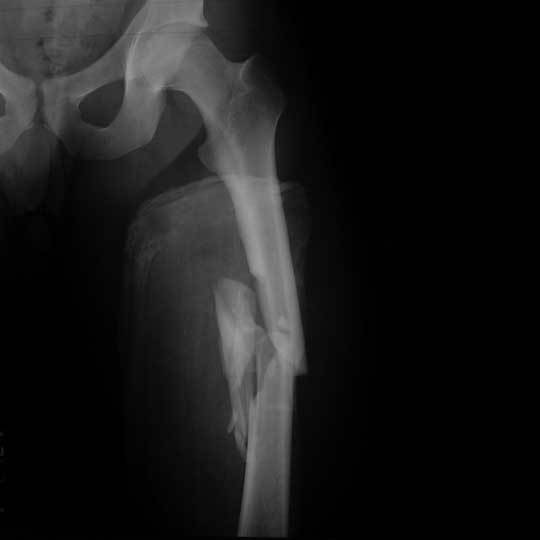

1. Long Bone

1. Found in the Legs

1. Femur

1. Tibia and fibula

1. is inferior to the

1. but superior to

1. Is made up of Epiphysis at the ends and Diaphysis in the middle (Shaft)

1. from outside to inside, the Cortex is the outermost layer

1. then Compact Bone

1. then the Periosteum

1. that all covers the Medullary cavity inside the bone

1. which contains yellow marrow and red bone marrow that creates red blood cells